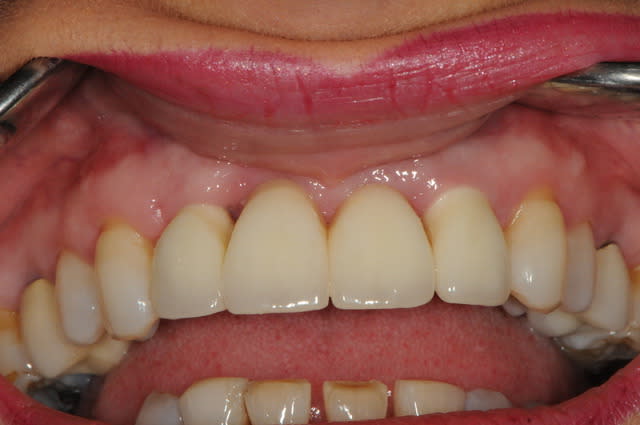

photo 1: j+1 mois et demi

la cigarette à repris de plus bel, je suis désespéré mais bon, avec la chir muco gingival je devrais y arriver.

photo 2: j+3 mois